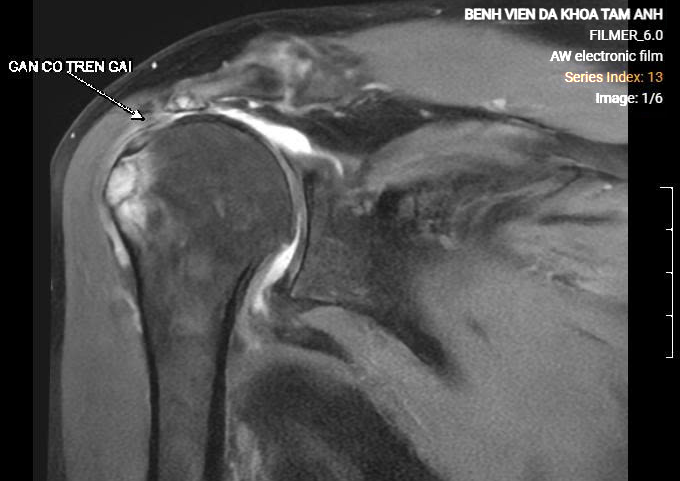

Doctor Nguyen Ngoc Tiep, Specialist II, from the Orthopedic Trauma Department at Tam Anh General Hospital Hanoi, stated that Van's shoulder MRI results showed a partial infraspinatus tendon tear and a complete supraspinatus tendon rupture, with fatty atrophy and the tendon end retracted 4 cm from its attachment point. Other rotator cuff tendons were inflamed and edematous.

Van's MRI scan revealed a complete and retracted supraspinatus tendon rupture. Photo: Tam Anh General Hospital |

The shoulder muscle system comprises four tendons: supraspinatus, infraspinatus, subscapularis, and teres minor. The supraspinatus muscle initiates arm elevation and abduction, while the infraspinatus muscle helps rotate the arm. Doctor Tiep explained that the long-standing supraspinatus tendon rupture caused Van's humeral head to lose its stable central position in the glenoid socket, gradually displacing upwards. This led to narrowing of the subacromial space, compressing surrounding soft tissue structures, causing pain and early joint degeneration. Patients primarily experience pain at night and in the morning because joint displacement and increased compression occur when they turn in their sleep.